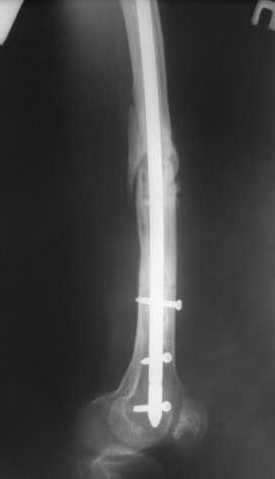

Пациенту М., 30-ти лет, 1,5 года назад в одной из московских больниц был выполнен остеосинтез бедренной кости штифтом UFN (диаметр штифта 9 мм).

К нам больной поступил с признаками ложного сустава бедренной кости, перелома

штифта и дистального блокирующего винта (images 1,2,3).